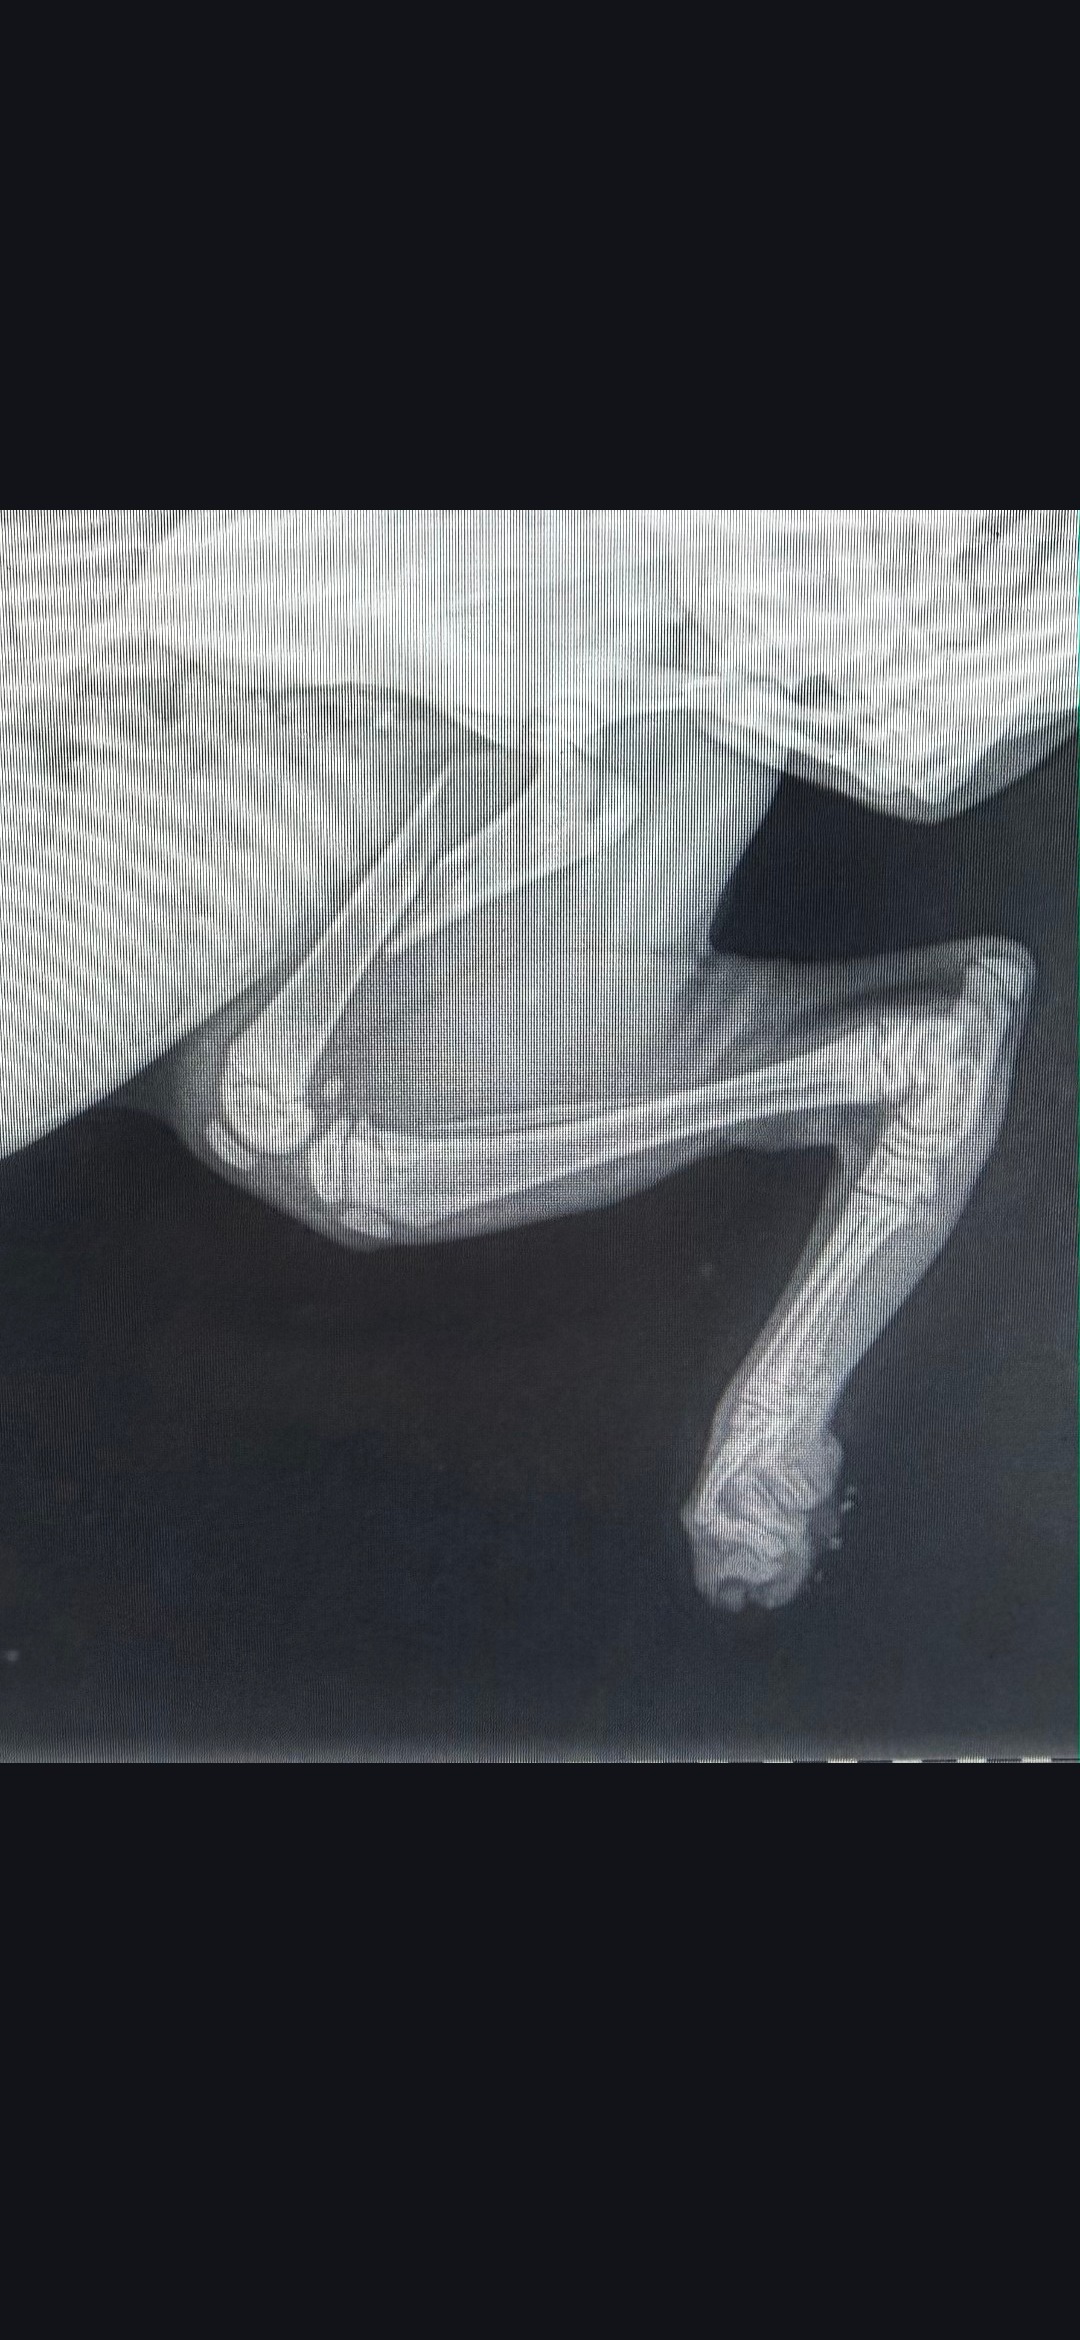

My kitten Nash is only 10 weeks old and has already faced a heartbreaking challenge. After falling from our second floor railing, Nash suffered a broken leg that will require orthopedic surgery. It’s been a scary and emotional time for both of us, and I’m doing everything I can to make sure Nash gets the care he needs to heal and thrive.